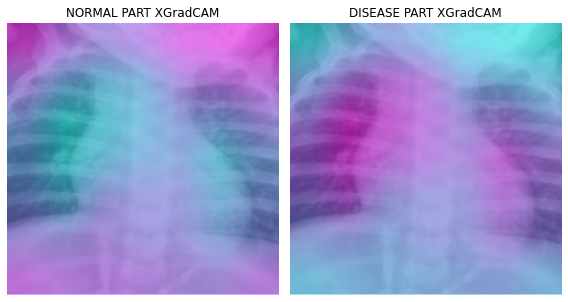

fig, (ax1,ax2) = plt.subplots(1,2)

dls.train.decode((x,))[0].squeeze().show(ax=ax1)

ax1.imshow(-cam_xgradcam.squeeze(),alpha=0.5,extent=(0,224,224,0),interpolation='bilinear',cmap='cool')

ax1.set_title("NORMAL PART XGradCAM")

#

dls.train.decode((x,))[0].squeeze().show(ax=ax2)

ax2.imshow(cam_xgradcam.squeeze(),alpha=0.5,extent=(0,224,224,0),interpolation='bilinear',cmap='cool')

ax2.set_title("DISEASE PART XGradCAM")

fig.set_figwidth(8)

fig.set_figheight(8)

fig.tight_layout()